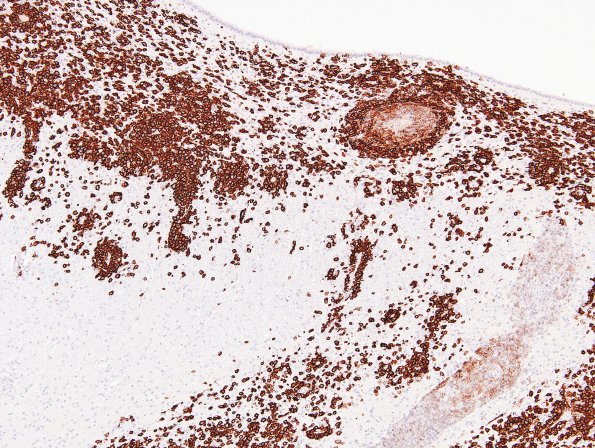

Washington University Experience | NEOPLASMS (HEMATOLYMPHOID) | Lymphoma, PTLD | 1E2 Lymphoma, B-cell (PTLD, Case 1) N3 CD20 1

1E2,3 Higher magnification images showing numerous, strongly immunoreactive B cell lymphoma (CD20 IHC)